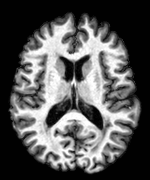

4.1 MS-100 Dataset

For this dataset, the training was performed separately with two sets of masks from the two raters of ISBI-21 data. Then two memberships were generated for each of the images. For each image, the two memberships were averaged and thresholded to form the final segmentation. Fig. 6 shows MR images and segmentations of subjects from the MS-100 dataset, where the subjects have high (cc), moderate (cc), and low (cc) lesion loads. For the subject with high lesion loads (#1), all methods performed comparably, although OASIS and LST underestimated some small and subtle lesions (yellow arrow). For the subject with moderate lesion load (#2), OASIS and S3DL underestimated some lesions (orange arrow) and LesionTOADS overestimated some (green arrow). When the lesion load is small and the FLAIR image has some artifacts (subject #3), LesionTOADS, S3DL, and OASIS produce a false positive (yellow arrow) in the cortex. LST shows underestimation, but FLEXCONN does not produce the false positive. The reason is partly because of the use of large patches, which can successfully distinguish between bright voxels in cortex and peri-ventricular regions.